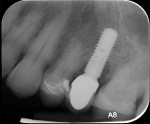

A healthy 58-year-old Caucasian male patient presented with extensive bone resorption, BoP, and suppuration affecting an implant placed in the maxillary left second premolar area (Figure 1). Probing depths were 6 mm on the mesial-buccal aspect, 6 mm on the mid-buccal aspect, 9 mm on the distal-buccal aspect, 5 mm on the mesial-palatal aspect, 3 mm on the mid-palatal aspect, and 4 mm on the distal-palatal aspect. Radiographic assessment revealed bone resorption of about 25% of the total length of the fixture on the mesial aspect and about 40% of the total length of the fixture on the distal aspect (Figure 2). Based on Froum and Rosen's classification of peri-implant disease,15 the patient was diagnosed with moderate peri-implantitis.

The peri-implant defect was then grafted with 1-cc cortico/cancellous particulate allograft. A 15-mm x 20-mm polylactic acid bioresorbable membrane was trimmed and adapted over the area, and the flap was sutured with 4-0 polytetrafluoroethylene (PTFE) in an attempt to obtain a primary closure (Figure 8).